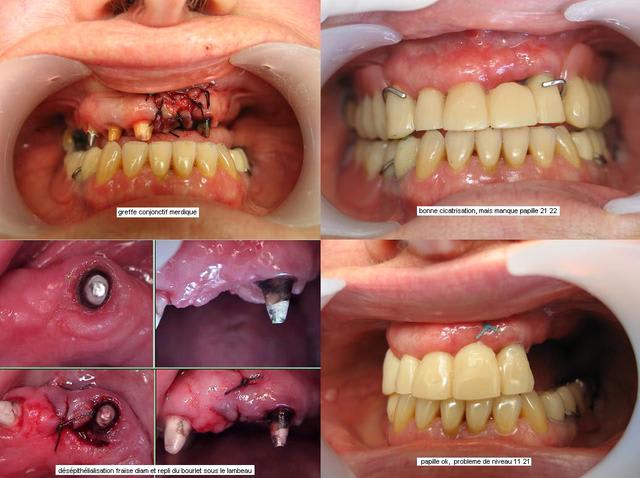

Un antre cas, pour faire plaisir à Jeff2 et montrer que le recentrage n'est pas systématique.

En fait, j'aurai pu mettre le cas en paro, à cause de la gestion de la gencive, mais je pense que le débat lui donne ça place ici.

Après avoir fait ouvrir grand, bien relaxé la patiente, elle restait dévié en ouverture max, et fermait direct en dévié : donc, j'ai choisi de reconstruire sans recentrer. ( les recentrages et propulsions que j'ai pu réalisé en technique clausade, pourtant validé en posturo, ne m'ont jamais vraiment satisfait )

A noter la gestion curieuse de l'esthétisme par mon prédécesseur !